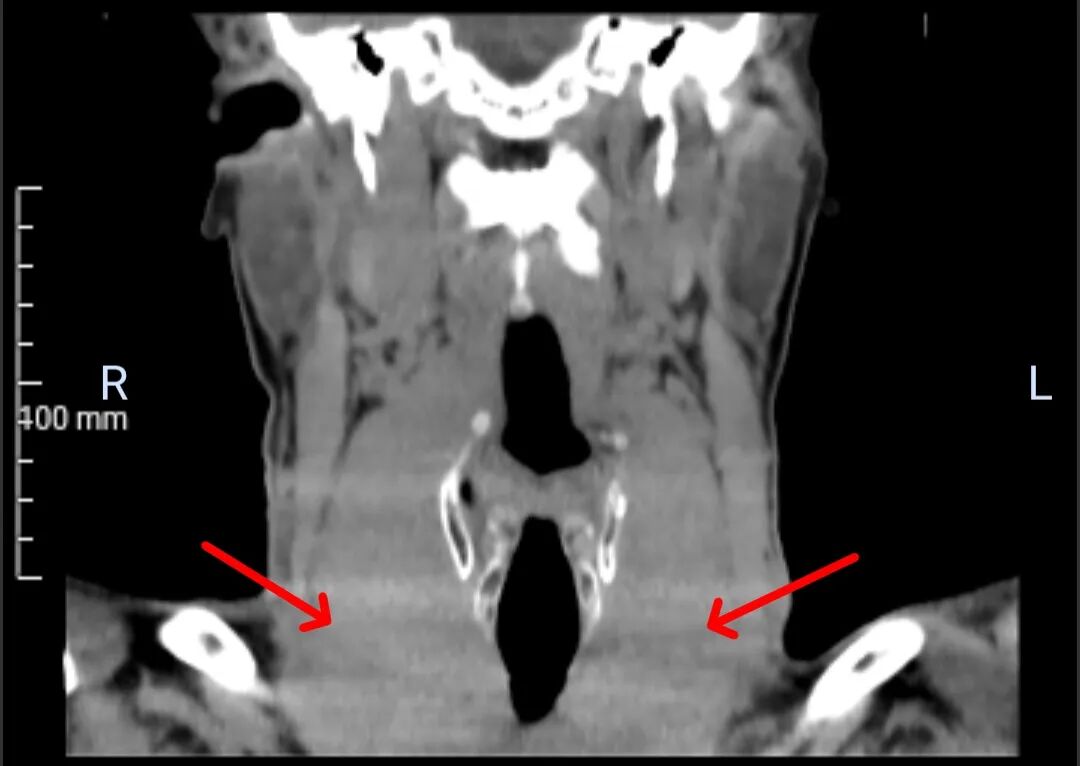

术前CT检查结果令人震惊:患者一侧甲状腺肿瘤直径已达9cm,另一侧更是巨大,直径10cm!如此巨大的肿瘤,手术难度和风险呈几何级数攀升。这无疑是一枚埋在颈部的“定时炸弹”,时刻威胁着患者的生命安全。